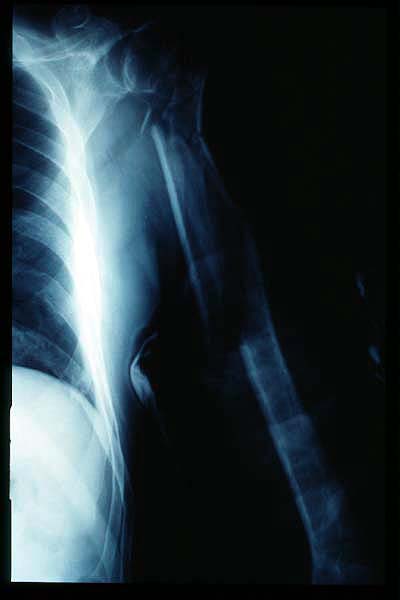

Fractura impactada de húmero .

Fractura de húmero, intensa desviación de fragmentos

Fractura de húmero.

Fractura compleja de húmero.